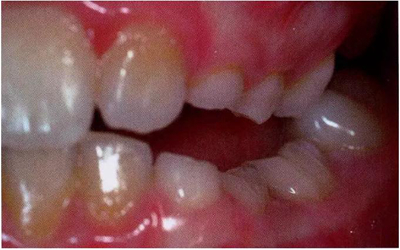

圖1:輕度下沉的臨床像